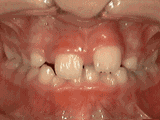

第四种

牙列拥挤,牙槽骨过窄,牙齿没有足够空间,只好前后左右高低上下乱长,经过矫正后的牙齿是这样的